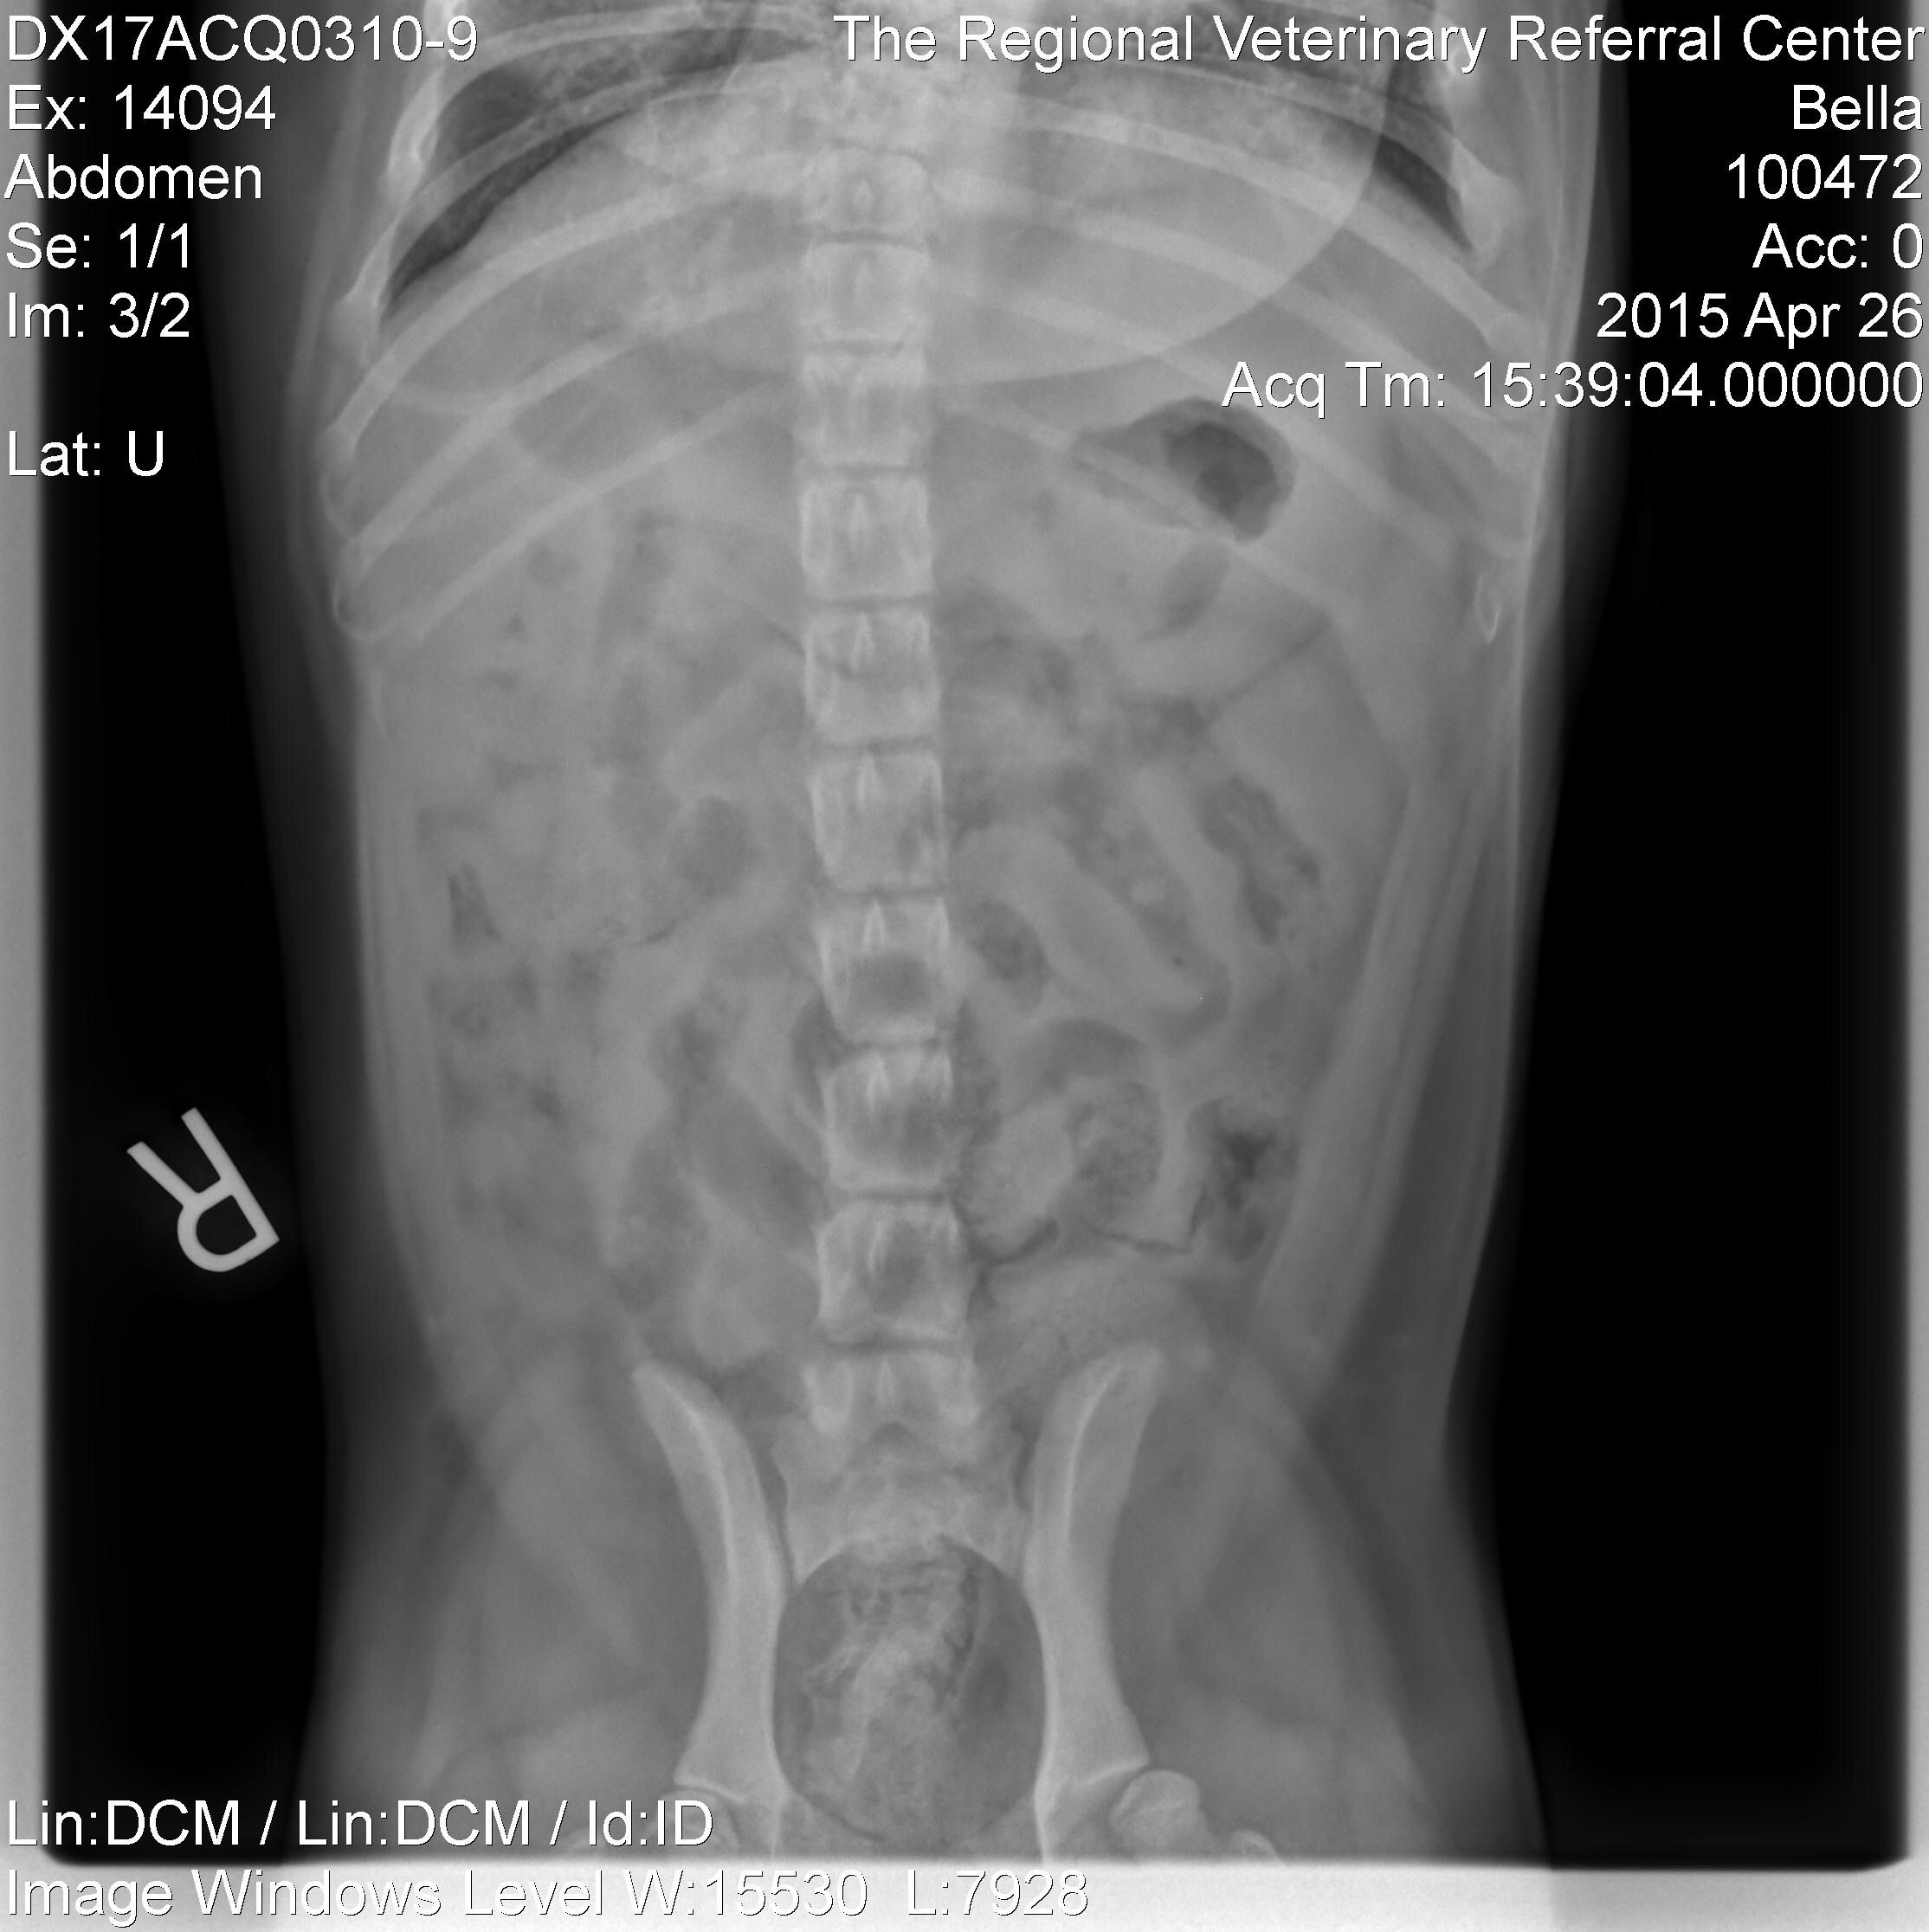

[MENTION=13133]TyTysmom[/MENTION] here are the xrays!

View attachment 86755View attachment 86756

The questionable item is a very faint sand dollar looking object in the lower right. It's identifyable only on the side picture, not on the back picture. What do you think??